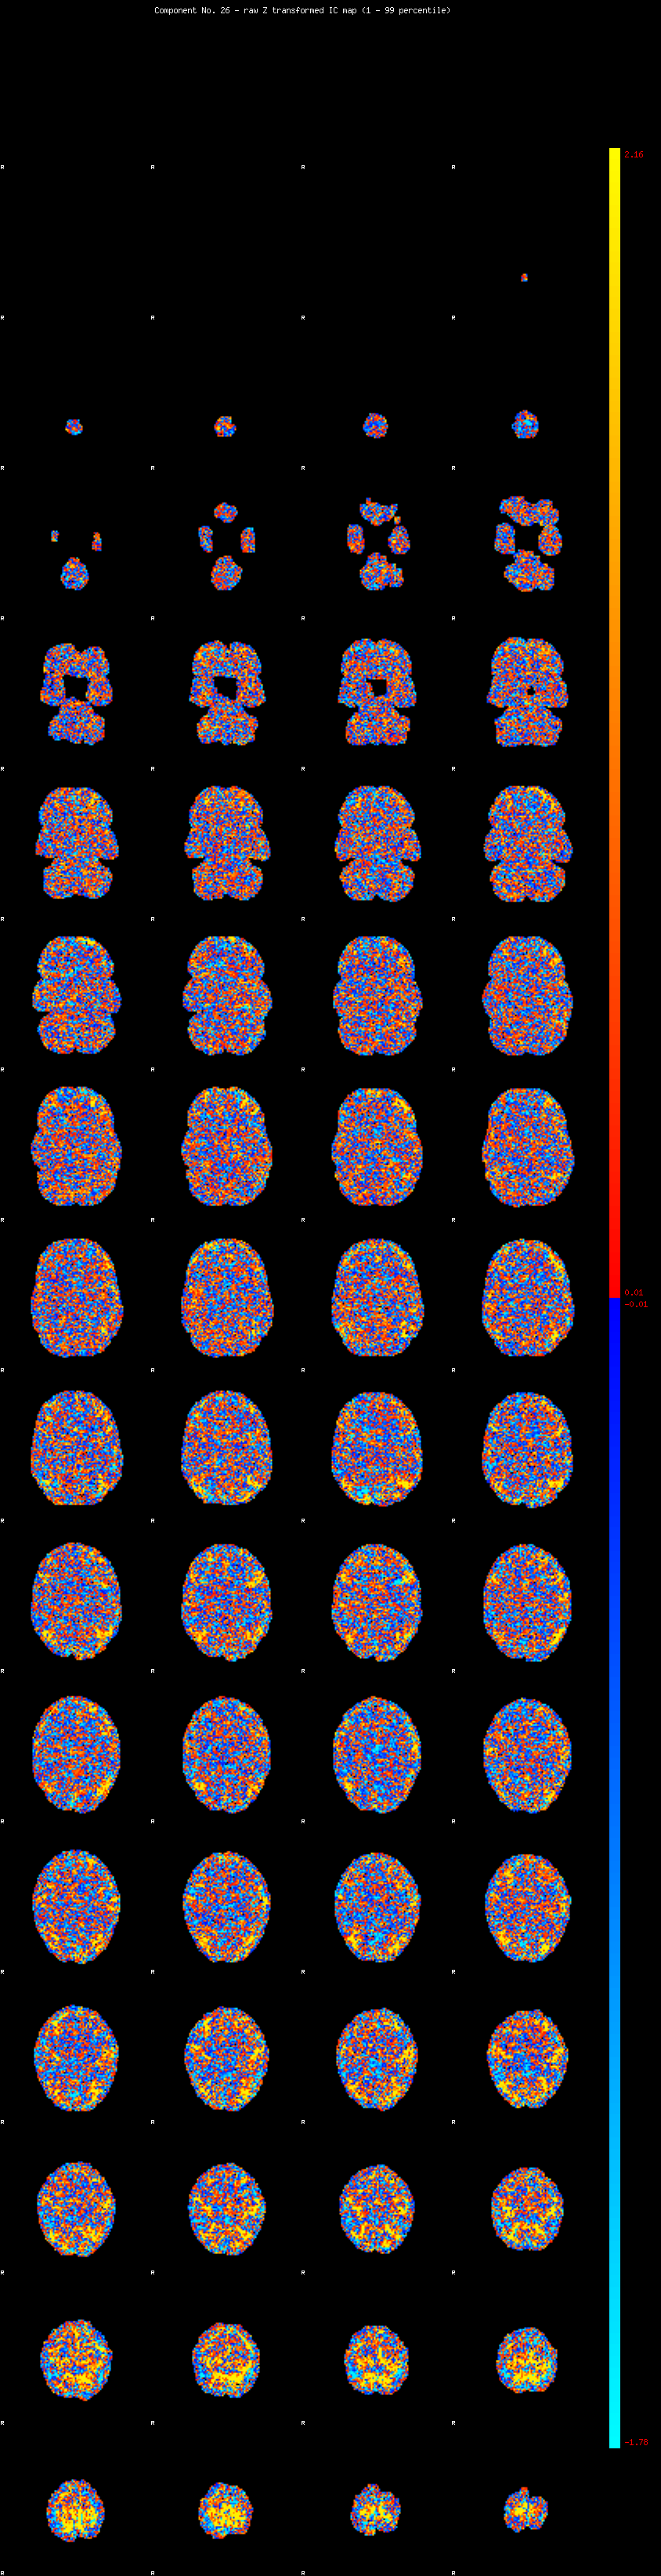

IC_26 Mixture Model fit

Means : 0.000000 3.019549 -2.755741

Vars : 1.000000 3.990694 0.919466

Prop. : 0.951665 0.041341 0.006994